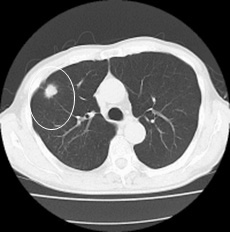

今度はCT撮影。骨盤と腹部撮影。

CTとはcomputed tomographyで、コンピューターによる断層撮影のこと。X線で身体の輪切りの画像を撮影すること。ドーナツ型の装置の中央に身体を置いて、周囲からX線を照射して、そのX線情報をコンピューターで解析して身体の断面の画像を得る。

単純CTで区別がつかない病変は、造影剤を使用することで明確にわかるそうだ。

「腸が捻れてるとか、そういうことはありませんでした。転移もありません。腹痛の理由が見当たりません。強いて言えば、盲腸のところに大きな結石があります。これが動いて、大腸を引っ掻くことがあります。そうすると胃まで痛くなります。そういう可能性は考えられます。今日のところは痛み止めを処方しますので、ずっと痛むようならば、来週に外来で外科の診察を受けてください」

そういえば、去年の手術前の主治医による断層撮影画像説明の時に、「盲腸のところに大きな石ができてますが、問題になっているわけではないので、今のところは放置でいいでしょう」と聞いた記憶があった。